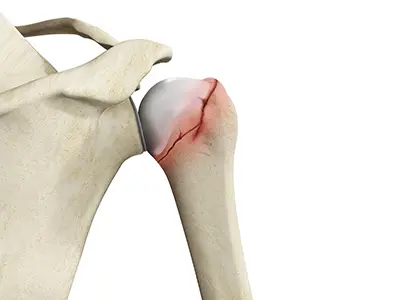

Proximal Humerus Fractures

Fractures of the proximal humerus are common in elderly individuals suffering from osteoporosis.